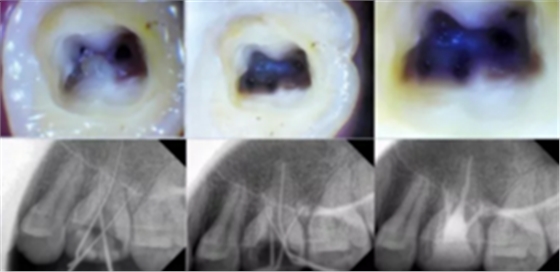

開髓去腐質(zhì)

根管治療開髓前必須去凈腐質(zhì),然后換用另一根新的車針(裂鉆或金剛砂車針均可,但金剛砂車針開髓震動感少,開髓穩(wěn))進(jìn)入髓腔,穿通髓腔后換高速球鉆揭頂,揭頂一定要全,以能看清整個髓室底為準(zhǔn),然后換用裂鉆或金剛砂車針修整髓壁。

這一步質(zhì)控的標(biāo)準(zhǔn)是:

①去凈腐質(zhì)和原有充填物。

②揭凈髓頂,看到整個髓底解剖結(jié)構(gòu)。

③髓壁與根管壁連續(xù)流暢。

④沒有牙頸部臺階,沒有過度切割髓壁和髓底。

2. X 線片

共有 4 張 X 線片,分別是術(shù)前、診斷絲 、主牙膠尖確認(rèn)、術(shù)后。

( 1 )術(shù)前:術(shù)前 X 線片用來了解牙齒的大概情況。術(shù)前預(yù)期為多根牙時 X 線片應(yīng)偏頭拍攝。

( 2 )診斷絲:根據(jù)術(shù)前 X 線片進(jìn)行開髓、根管的初步預(yù)備后,需要插入診斷絲,用來指示工作器械位置。常用 10 號或 15 號擴大器作為診斷絲插入牙髓腔。

( 3 )主牙膠尖確認(rèn):通過術(shù)前預(yù)期和診斷絲診斷,明確工作長度、牙根走向,進(jìn)行根管預(yù)備。之后應(yīng)進(jìn)行主牙膠尖(中銼)確認(rèn),已明確根管是否適合充填。

( 4 )術(shù)后:觀察治療效果。